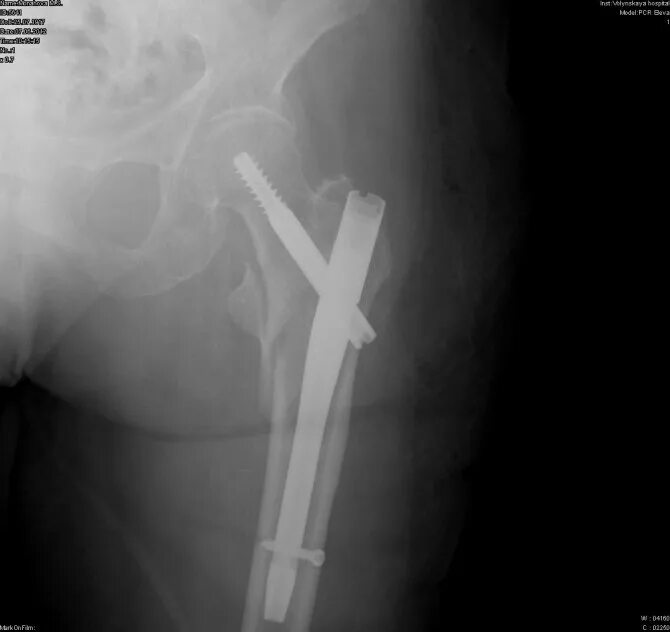

Остеосинтез чрезвертельного перелома